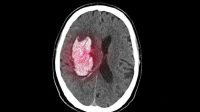

Penyebab-Gejala Pendarahan Otak yang Diderita Indra Bekti

bacakita.id, JAKARTA | Presenter Indra Bekti dilarikan ke rumah sakit usai tak sadarkan diri pada […]